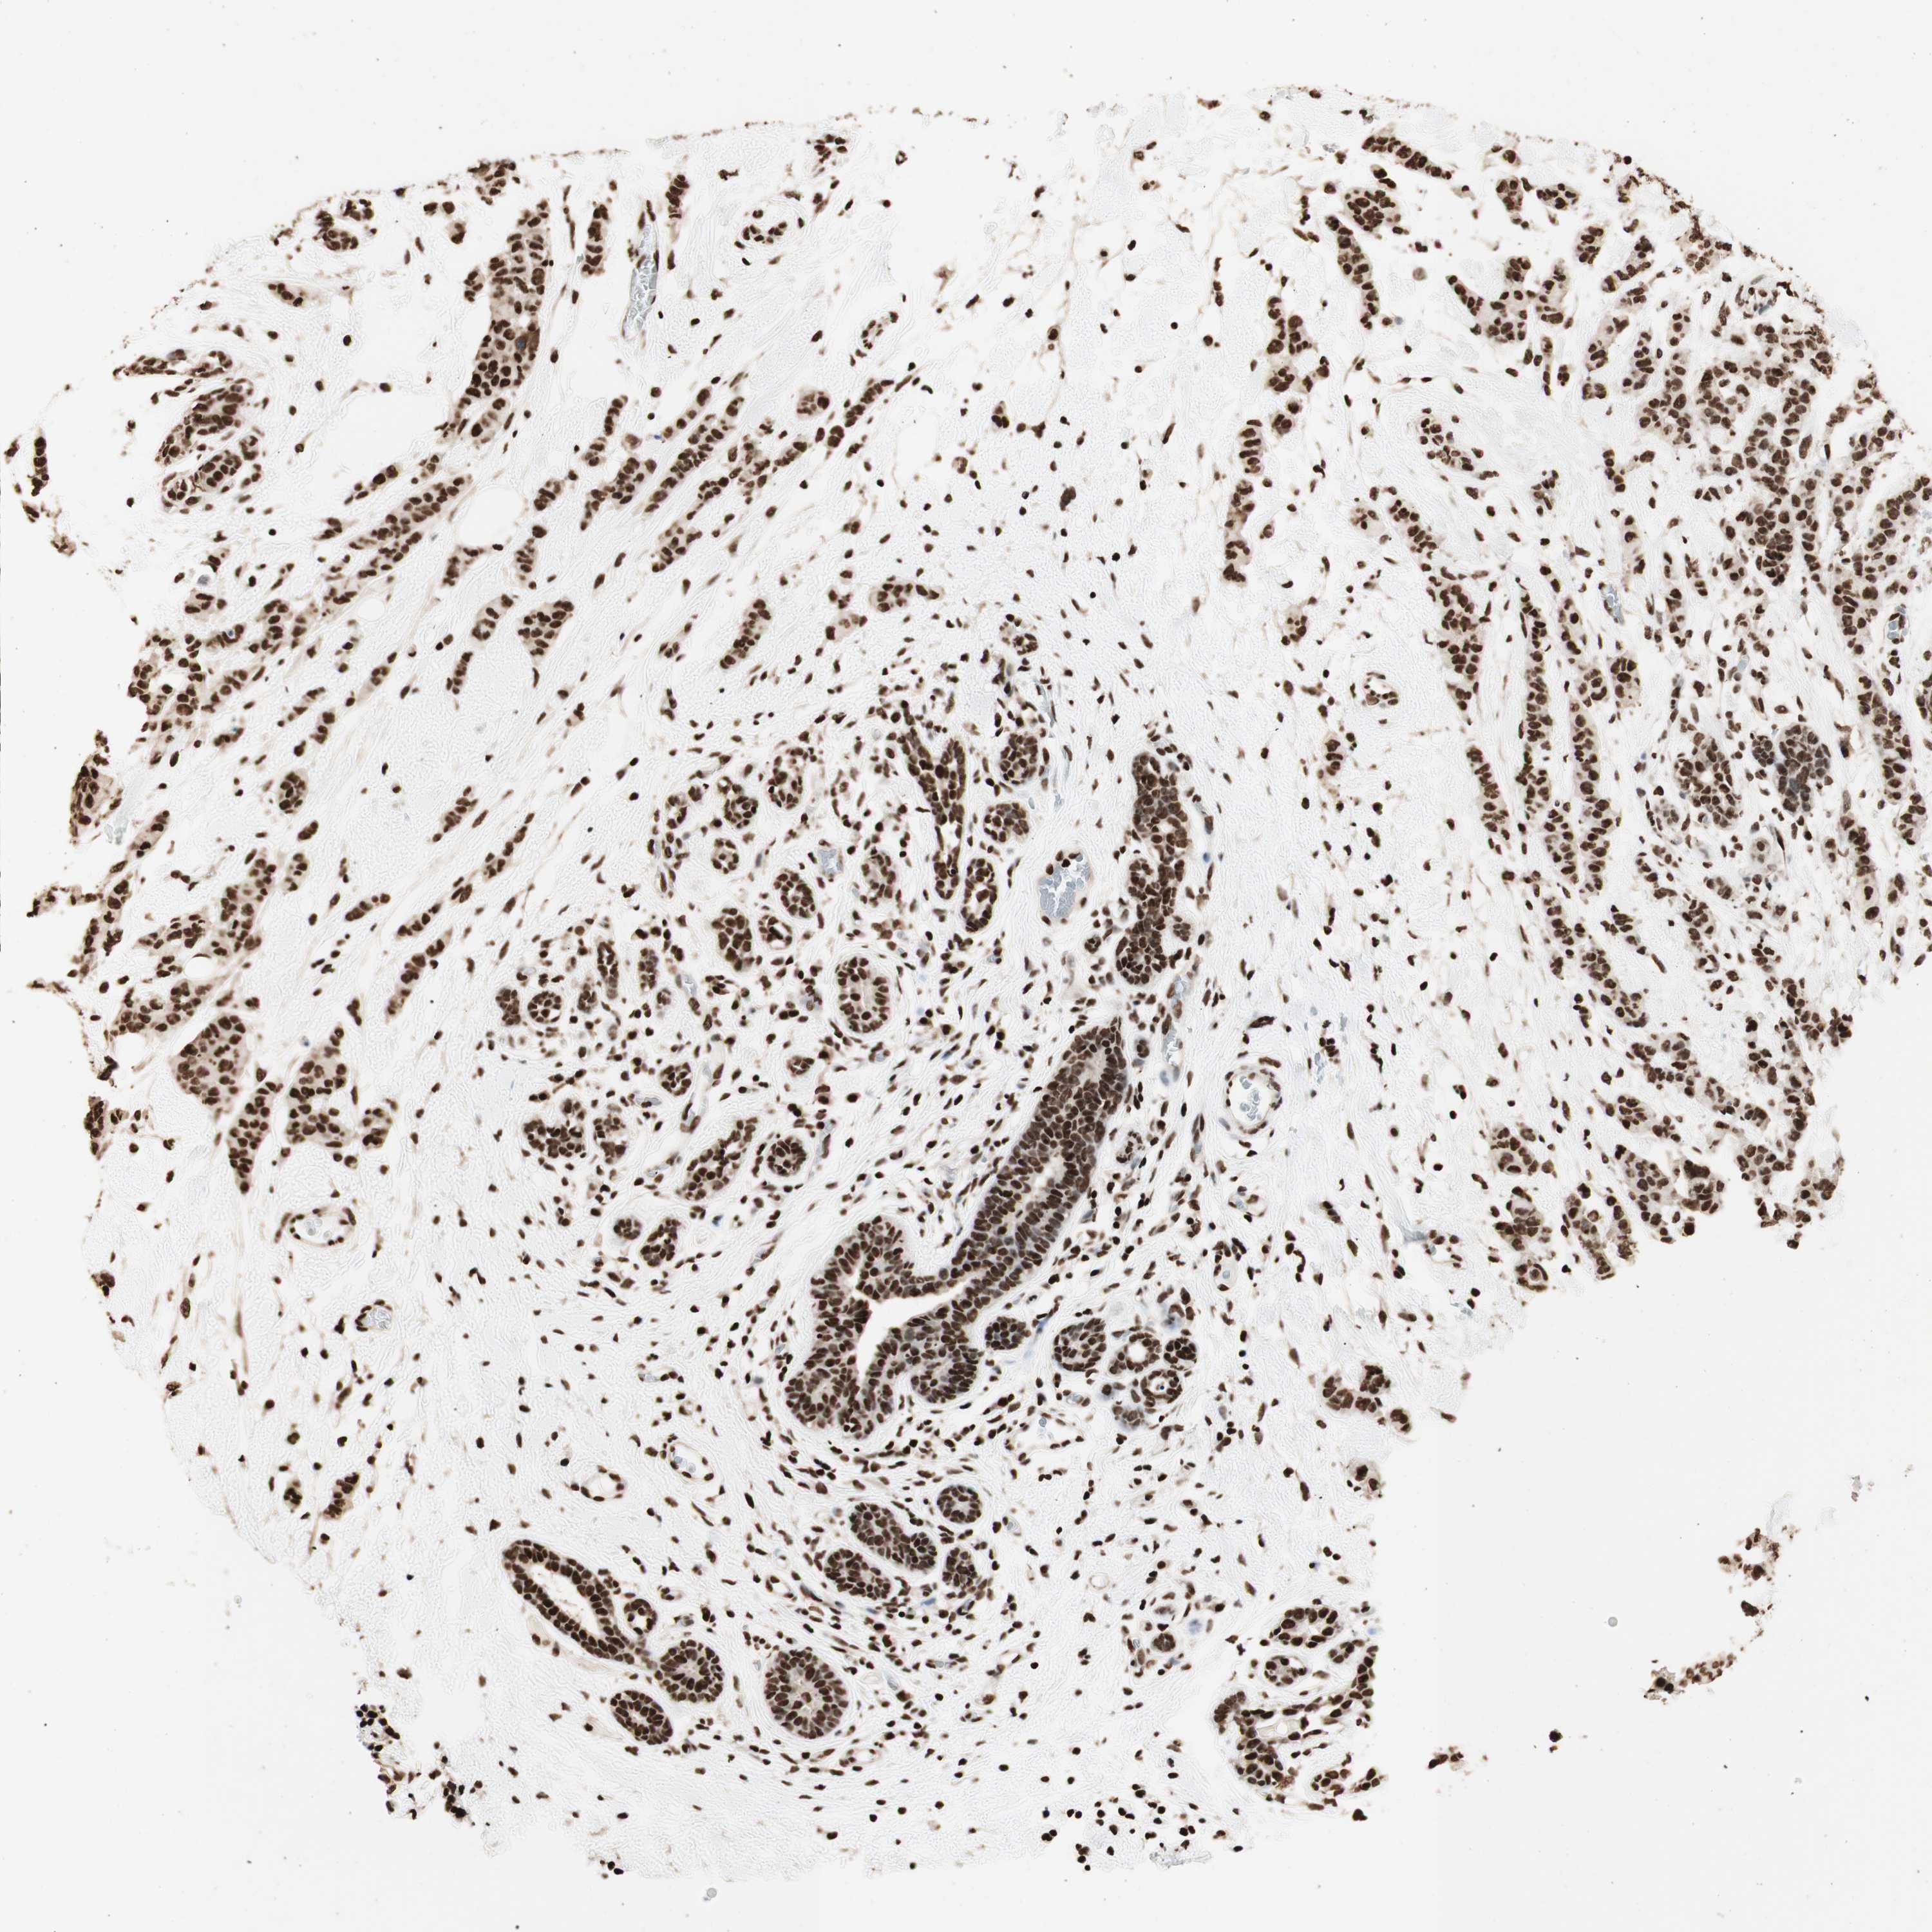

BRCA TCGA BRCA VALIDATION PROTEIN EXPRESSION